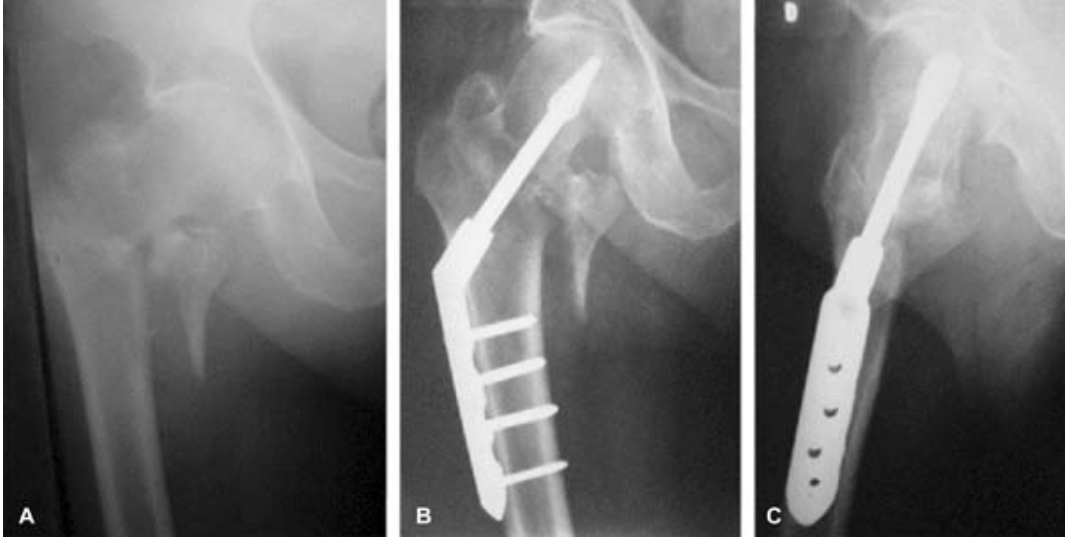

Osteossíntese de Fraturas de Fêmur Proximal e Diafisárias

• Sentar no leito logo que possível (pode ser no 1º dia)

• Sentar fora do leito no 2º dia e em pé sem carga

• Antibioticoprofilaxia

• Profilaxia TEV no 1º dia

• Dreno de sucção por 48 horas. Se débito > 400 mL/12h, avisar ortopedista

• Curativo apenas se estiver sujo e realizado pelo médico ou enfermeiro

• Exercícios isométricos

• Exercícios de movimentação do membro inferior e quadril no 2º dia

• Retirar SVD no 2º dia